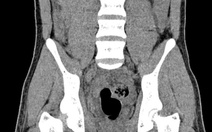

Các bệnh nhân nhập viện trong tình trạng đa chấn thương nặng, gồm: chấn thương vùng đầu, mặt; nhiều người rách da, dập nát mô mềm, xuất huyết dưới da, tụ máu phần mềm; gãy xương chi, chấn thương ngực, bụng. Có bệnh nhân khó thở, tụt huyết áp khi nhập viện.